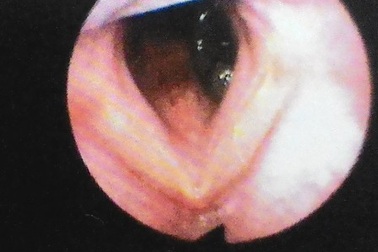

Ho ra máu vì đỉa suối cư ngụ trong cuống họngSuốt 1 tháng sau ngày tắm suối, nam bệnh nhân có biểu hiện ho ra máu, cảm giác khó thở, vướng, rát ở cuống họng. Tại bệnh viện, bác sĩ tiến hành nội soi gắp ra một con đỉa dài 3cm trong sự kinh ngạc của người bệnh.

Kinh hoàng đỉa trâu sống ngoe nguẩy trong cổ họng bệnh nhân nhiều ngàyKhi các bác sĩ tiến hành nội soi gắp trong cổ họng bệnh nhân, con đỉa vẫn ngoe nguẩy. Con đỉa được gắp ra dài tới 10cm, to gần bằng ngón tay là thủ phạm khiến cả tháng nay bệnh nhân ho nhiều, khó thở, ho ra máu.

Gắp 1 con đỉa 15cm trong thanh quản một thanh niênChiều ngày 13/6, Bệnh viện Thái An, TP Vinh, Nghệ An nội soi gắp 1 con đỉa dài 15cm ở trong thanh quản của bệnh nhân nam.